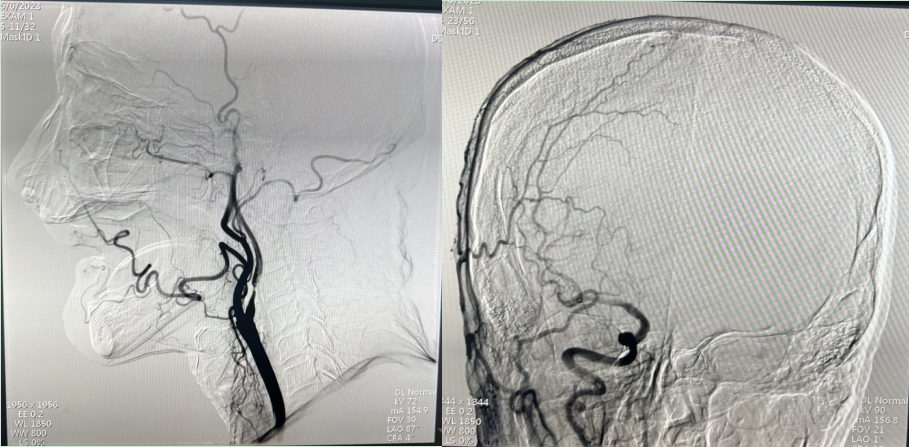

图一:支架植入术前